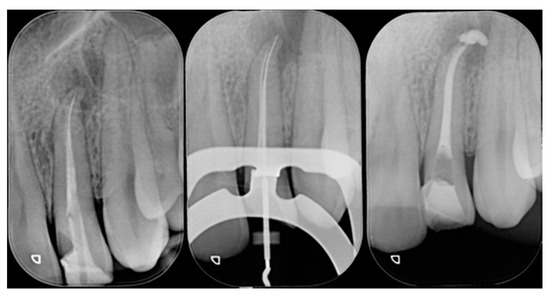

Figure 2.

Initial x-ray. Reprinted from Restauri diretti nei settori anteriori, G. Paolone, S. Scolavino, © 2021, with permission from Quintessence Publishing Italy.

Figure 21.

Initial x-ray, during and after endodontic retreatment. Reprinted from Restauri diretti nei settori anteriori, G. Paolone, S. Scolavino, © 2021, with permission from Quintessence Publishing Italy.